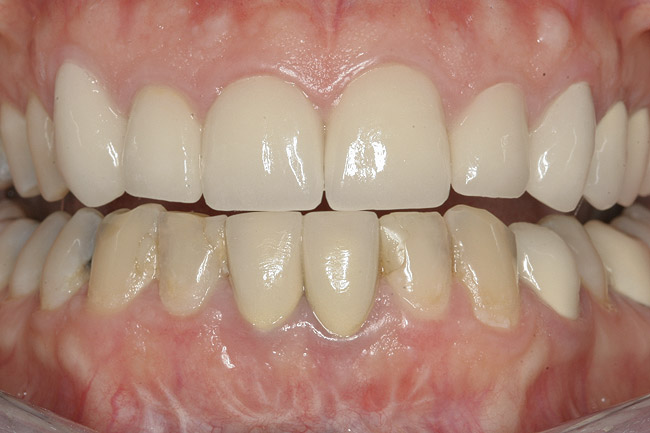

Figure 1  Initial presentation with yellow, poorly color-matched restored mandibular anterior teeth.

Figure 1

Figure 7  Finished feldspathic crowns, teeth Nos. 22, 23, 27, 28, and implant sites 24 through 26 showing good gingival emergence profile—post-cementation facial view.

Figure 7

Figure 8  Full smile—finished feldspathic crowns on teeth Nos. 22, 23, 27, and 28; implant crowns in sites 24 through 26; esthetic harmonization with opposing dentition.

Figure 8

This patient faced a unique situation, perhaps not previously reported: retaining a healthy mandibular lateral incisor knowing this would create an esthetic compromise. Indeed, while the discrepancy in gingival-margin height is noticeable in retracted view (Figure 7), it does not show in full smile (Figure 8).